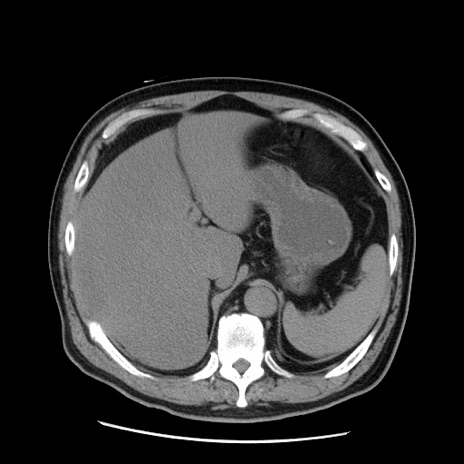

症例20(横断像)

【症例】 60歳代男性

【主訴】 腹部膨満、嘔吐

【現病歴】5日前頃より倦怠感を認め食事量減少し4日前の朝嘔吐、食事摂取困難となった。 3日前近医受診し点滴施行され整腸剤などを処方された。 当日他院を受診し、腹部膨満著明、炎症反応の上昇(CRP10.8、WBC11200)あり、紹介受診となる。

【身体所見】 意識JCS1 受け答えがはっきりしないBP 111/57mHg、 P 67bpm、、BT35.2°C、SpO2 97%(RA)、 腹部:膨隆、打診で鼓音あり、全体的に圧痛有り、腸蠕動音(-)、反跳痛ははっきりせず。

【データ】WBC 11400、CRP 14.20